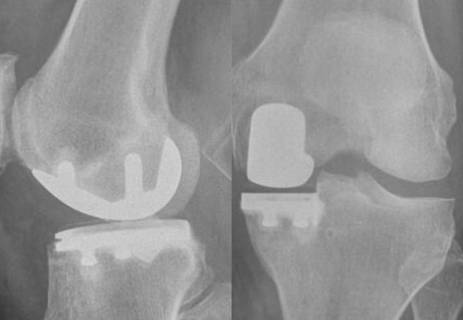

Hoe meer ervaring met halve knieprotheses, hoe minder kans op complicaties

Snel herstel na heup- en knieprotheses met programma ‘Rapid Recovery’